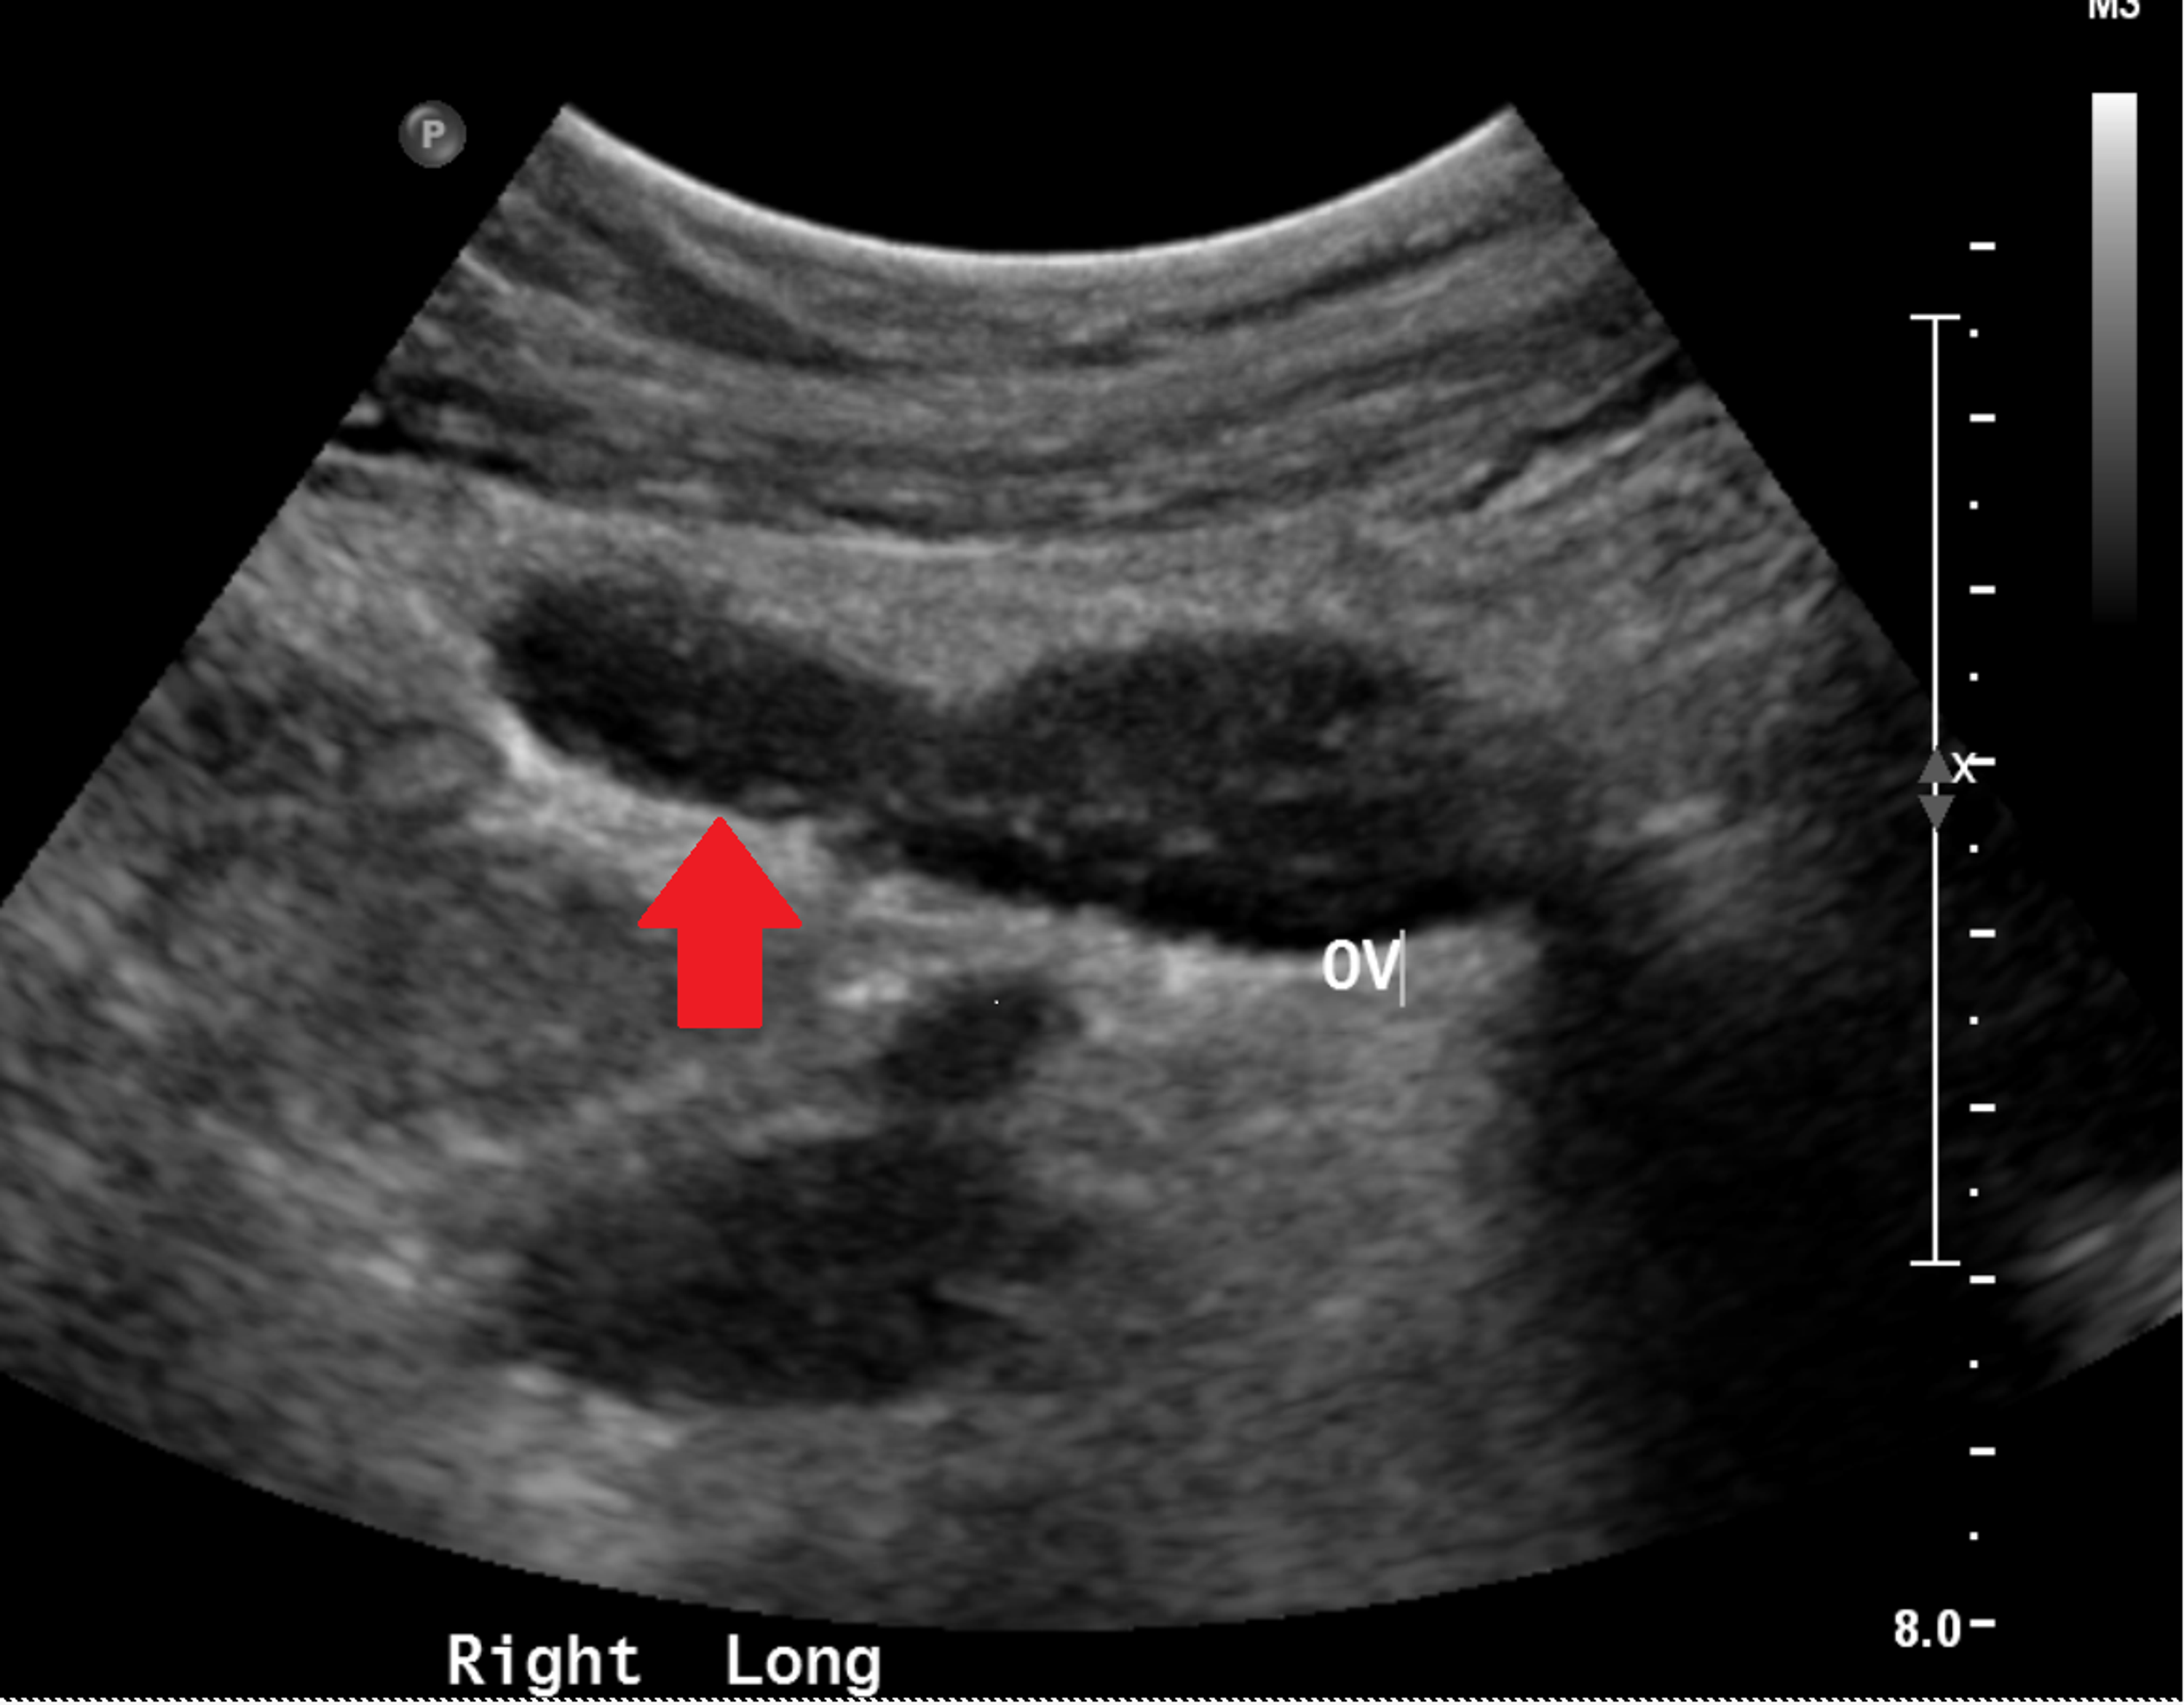

Ascites xray and CT Radiology at St. Vincent's University Hospital Spinning Top Radiology Unusual dilatation of urethra, giving “spinning top” appearance. An anteroposterior image from the voiding phase shows focal dilatation of the posterior urethra between the internal and. It is commonly regarded as a normal. Spinning top urethra (stu) is a term used to describe a widened posterior urethra seen mainly in girls. Spinning top urethra is a rare deformity, characterized by. Spinning Top Radiology.